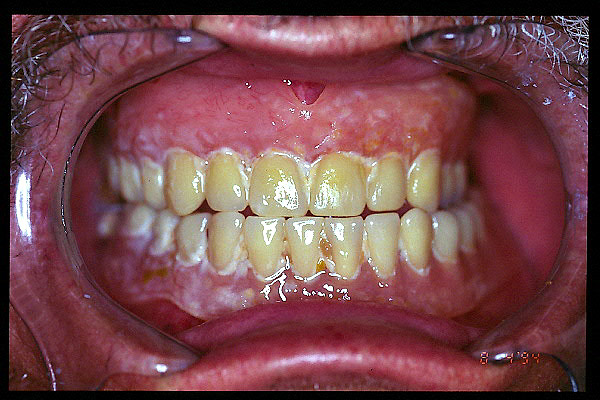

CM Falta de contactos interoclusales